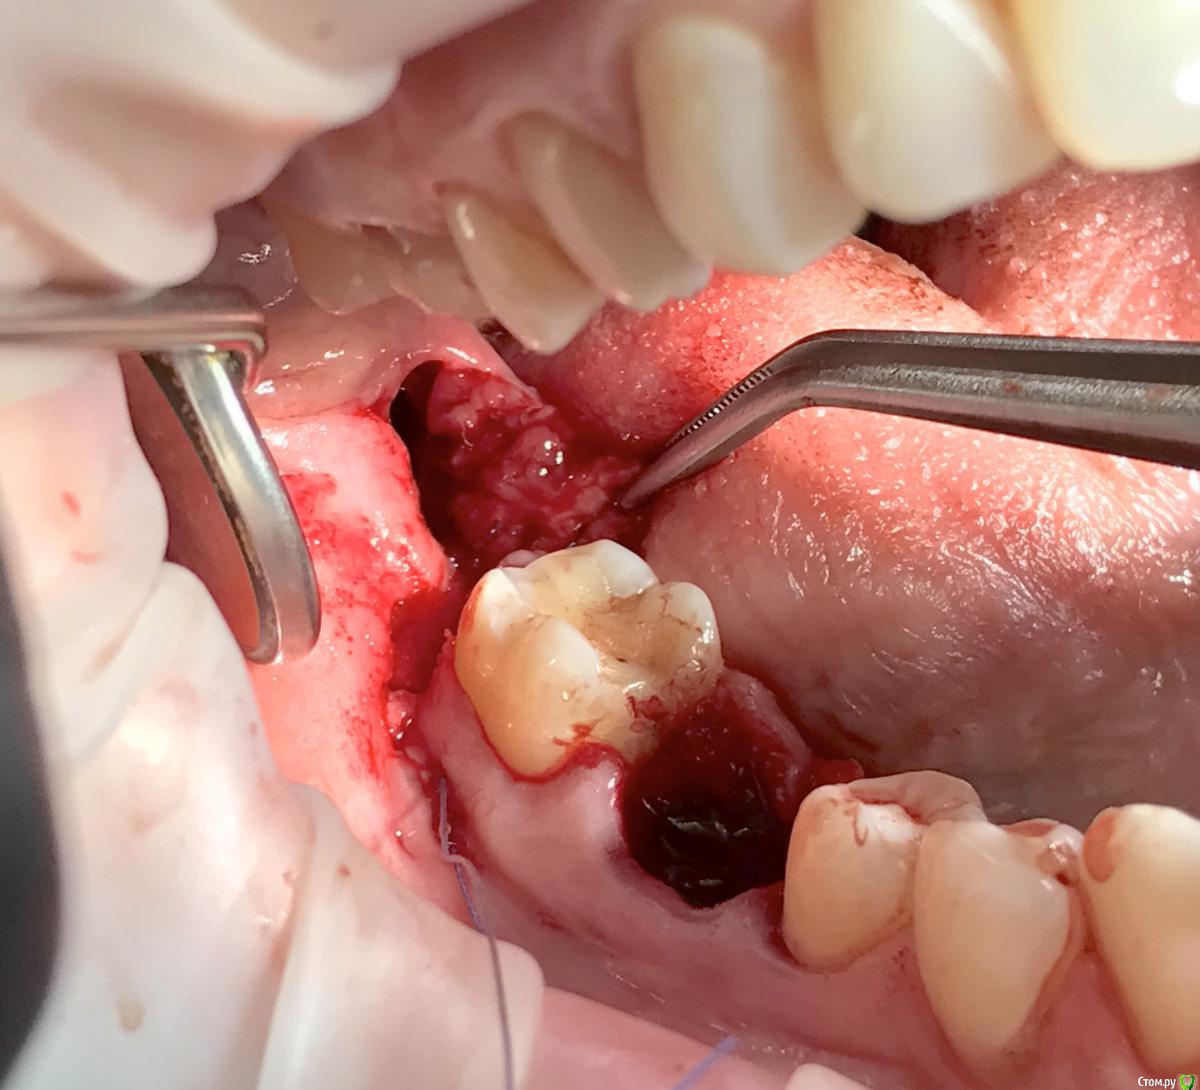

колесников Опубликовано 1 апреля, 2017 Автор Поделиться Опубликовано 1 апреля, 2017 Из свежего Ссылка на комментарий

колесников Опубликовано 2 апреля, 2017 Автор Поделиться Опубликовано 2 апреля, 2017 Тройной лоскут , вид через 5 -7дней. Снимок "до". И благодарность за скорое заживление 6 Ссылка на комментарий

колесников Опубликовано 16 апреля, 2017 Автор Поделиться Опубликовано 16 апреля, 2017 Иногда кажется ,что лоскут выделить язычно не возможно и наглухо ушить не удасться,особенно в случаях когда 8ка полностью прорезалась. Это только так кажется. Ссылка на комментарий

колесников Опубликовано 17 апреля, 2017 Автор Поделиться Опубликовано 17 апреля, 2017 (изменено) В данном случае развёрнутый. Опрокинутый когда 8ка не прорезалась,самый простой вариант. Да,в щели вижу всю проблему вторичного инфицирования,для прикрытия вероятного расхождения краев раны за 7кой,делаю второй лоскут. Изменено 17 апреля, 2017 пользователем колесников Ссылка на комментарий

колесников Опубликовано 6 мая, 2017 Автор Поделиться Опубликовано 6 мая, 2017 Воспользовался случаем попрактиковаться в выделении язычного лоскута. Разрез поверхностный,далее расщепление и выделение.По поводу лоскута без графта. Дважды пришлось так поступить. В первом случае расхождение краев за 7кой с образованием щели и застревание пищи. Во втором случае мезиально все герметично,дистально (?) щель,при зондировании -пусто. Итого: лоскут без графта-так себе вариант. Ссылка на комментарий